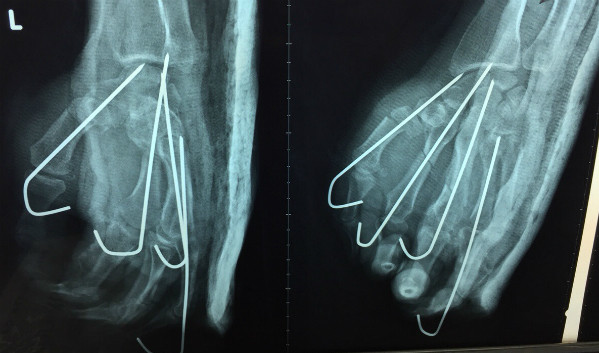

Ảnh chụp X-quang sau mổ của bệnh nhân. Ảnh bệnh viện cung cấp.

Ông Mai bị đứt lìa tay trái, bác sĩ bệnh viện Chấn thương Chỉnh hình TP HCM đã phẫu thuật nối song vẫn hoại tử một ngón.

Theo bác sĩ Thạch, tiên lượng nguy cơ hoại tử bàn tay đứt lìa sau nối rất cao vì tổn thương ban đầu quá trầm trọng. Hơn 10 ngày sau mổ, hiện bàn tay bệnh nhân hoại tử một ngón, chỉ cứu được ngón cái, ngón trỏ, ngón giữa.